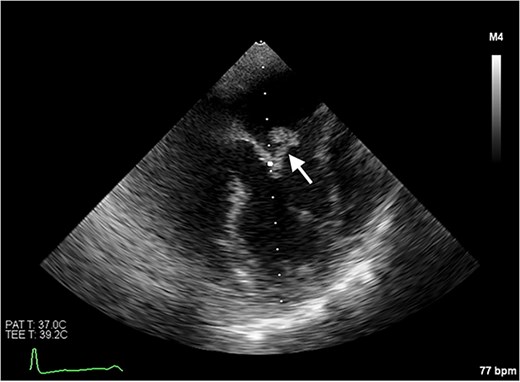

Despite initially recovering well postoperatively, she decompensated on postoperative day 5. Blood cultures and 16S polymerase chain reaction (PCR) testing were negative. Transoesophageal echocardiography (Fig. 6) demonstrated severe bioprosthetic mitral valve dysfunction characterised by extensive thrombus on the mitral leaflets, in the left atrium, and the inferior vena cava. A small mobile mass was also observed on the aortic valve’s non-coronary cusp. Subsequent hepatic biopsy showed metastatic adenocarcinoma. The patient unfortunately passed away; post-mortem examination confirmed metastatic pulmonary adenocarcinoma with thrombotic paraneoplastic syndrome.

Transoesophageal echocardiogram showing thromboses on the bioprosthetic mitral valve leaflets, as well as in the left atrium and the inferior vena cava. Thrombus is also visible on the non-coronary cusp of the aortic valve.